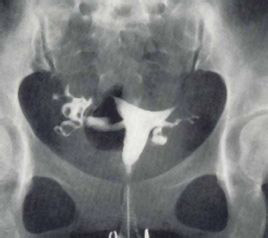

| 子宫附件B超 | 彩超检查女性子宫附件的基本情况和相关疾病的初步诊断 |